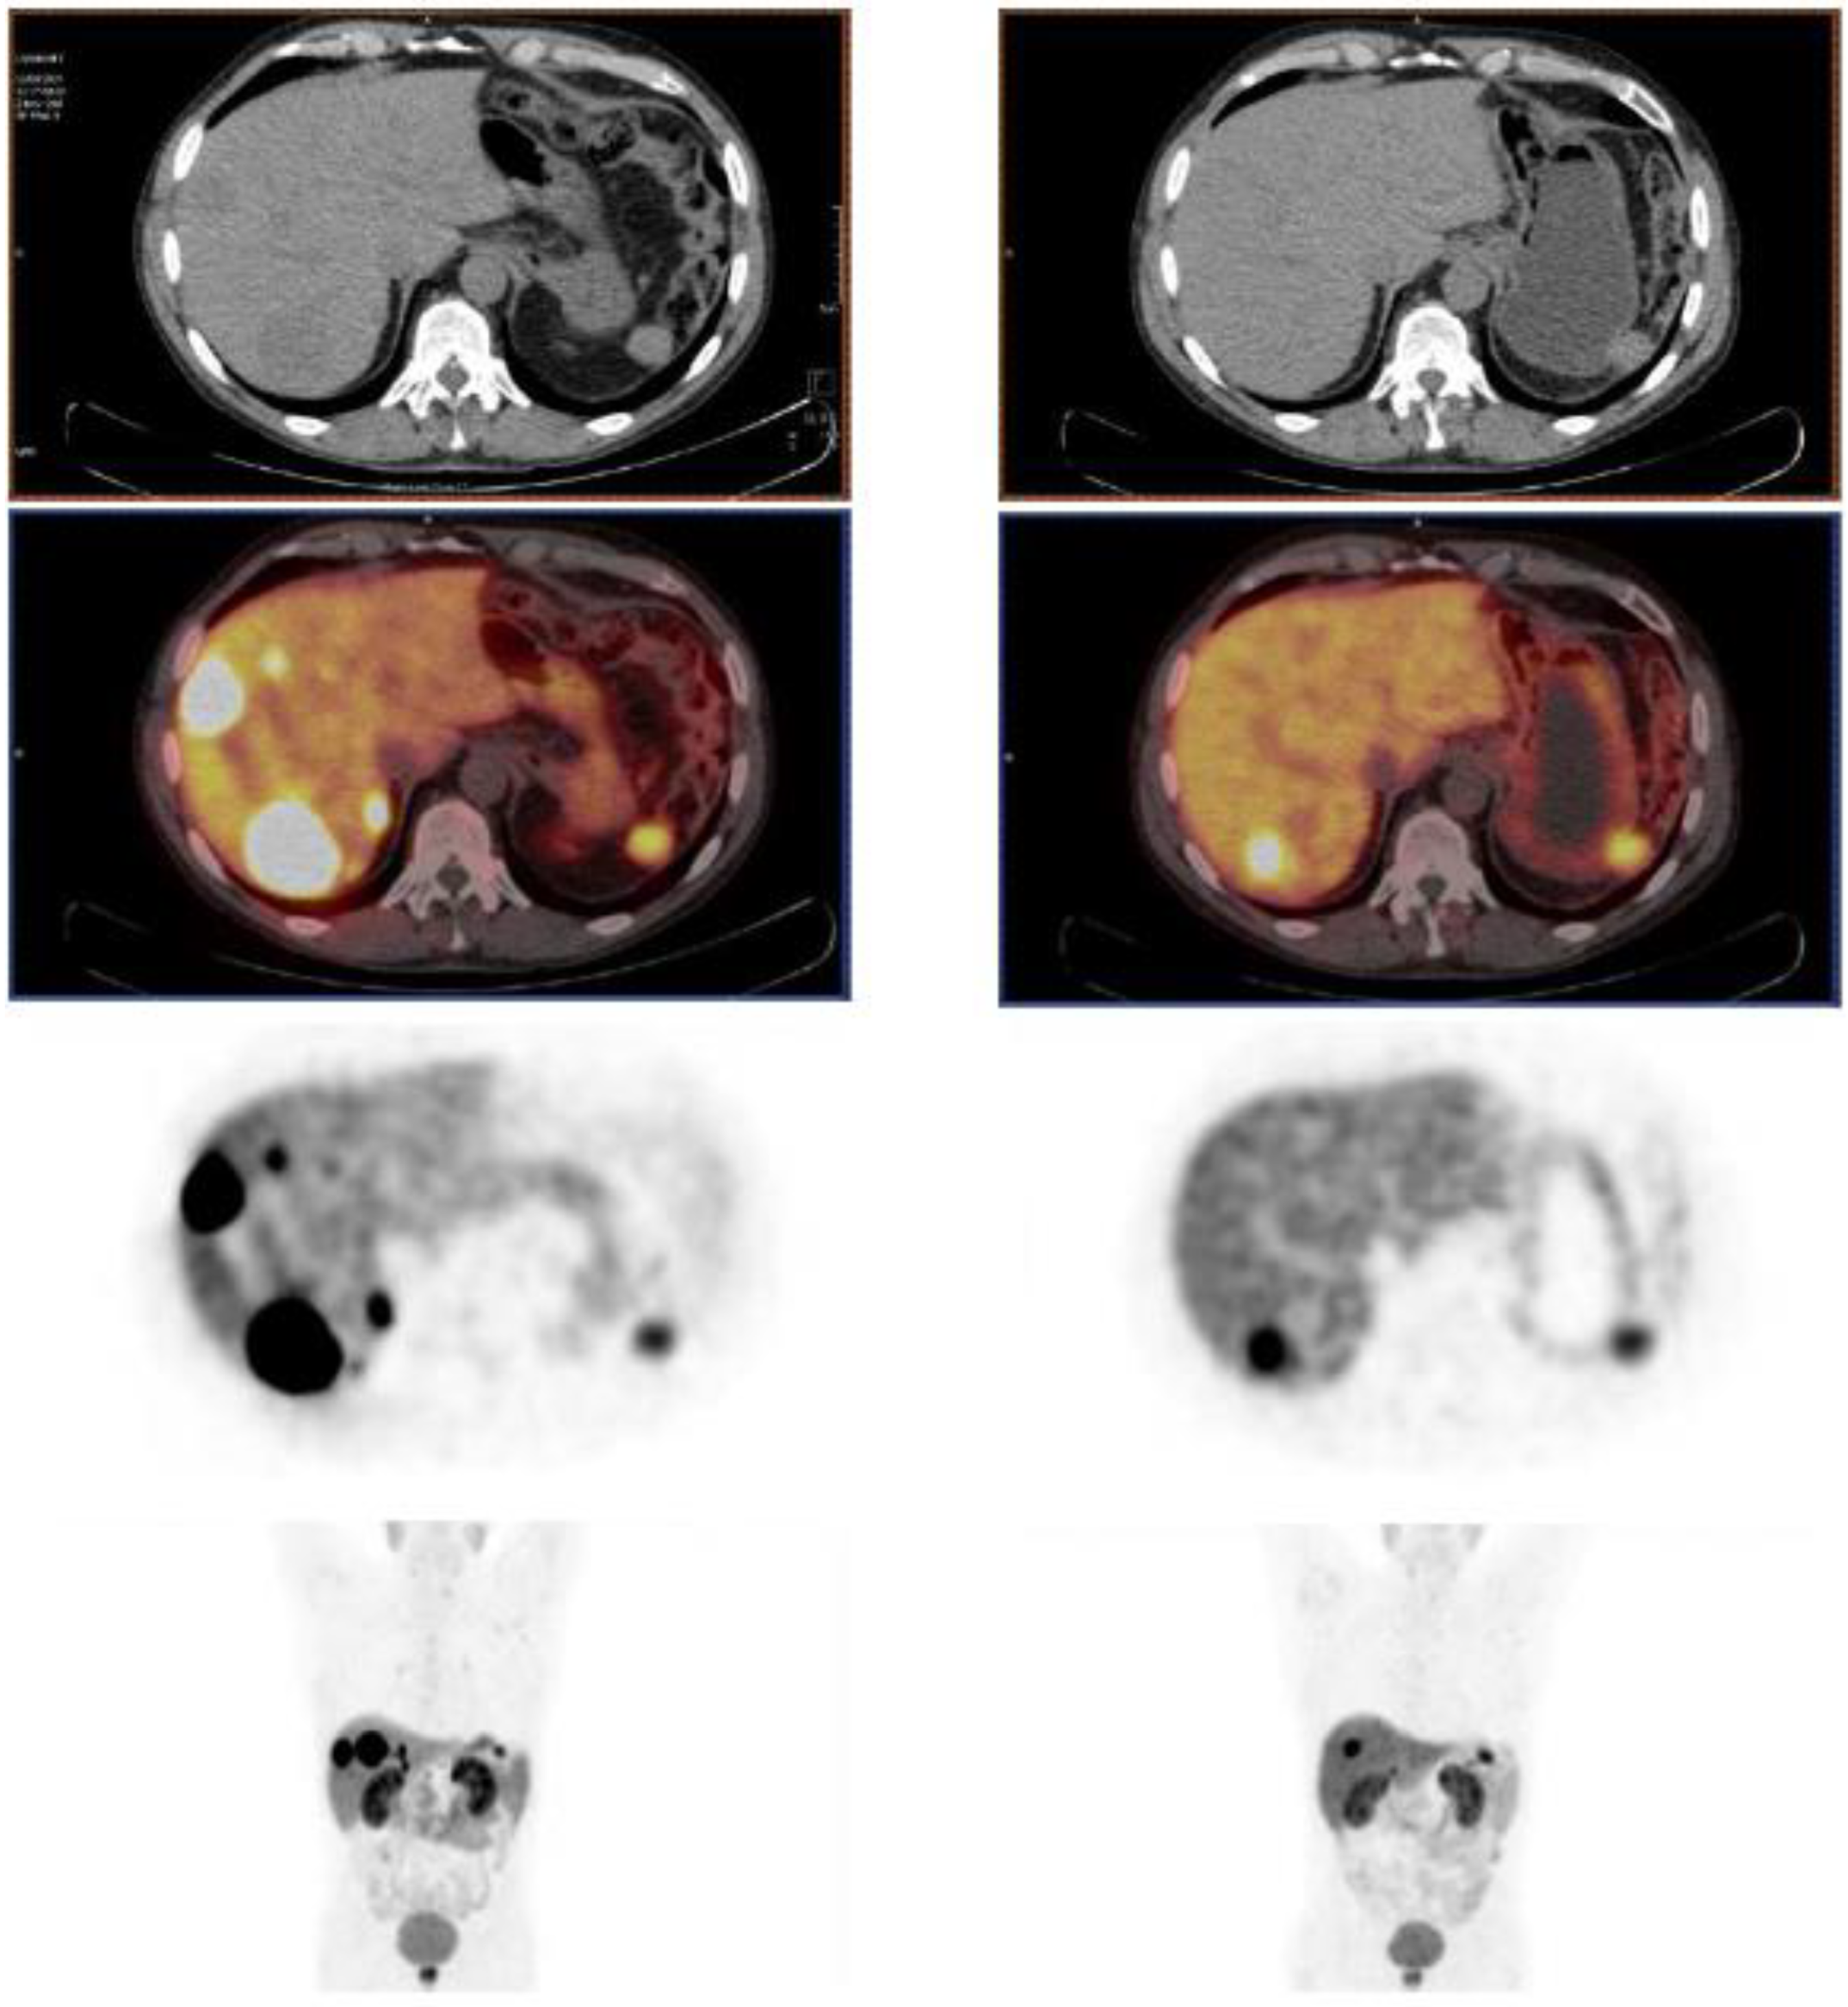

- Zhang, J.; Kulkarni, H.R.; Baum, R.P. Peptide Receptor Radionuclide Therapy Using 225Ac-DOTATOC Achieves Partial Remission in a Patient with Progressive Neuroendocrine Liver Metastases after Repeated β-Emitter Peptide Receptor Radionuclide Therapy. Clin. Nucl. Med. 2020, 45, 241–243. [Google Scholar] [CrossRef]

- Alan Selçuk, N.; Demirci, E.; Ocak, M.; Toklu, T.; Ergen, S.; Kabasakal, L. Almost Complete Response with a Single Administration 225Ac-DOTATATE in a Patient with a Metastatic Neuroendocrine Tumor of Unknown Primary. Mirt 2022, 31, 139–141. [Google Scholar] [CrossRef]

- Satapathy, S.; Sood, A.; Das, C.K.; Kavanal, A.J.; Mittal, B.R. Alpha Before Beta: Exceptional Response to First-Line 225Ac-DOTATATE in a Patient of Metastatic Neuroendocrine Tumor with Extensive Skeletal Involvement. Clin. Nucl. Med. 2022, 47, e156–e157. [Google Scholar] [CrossRef] [PubMed]